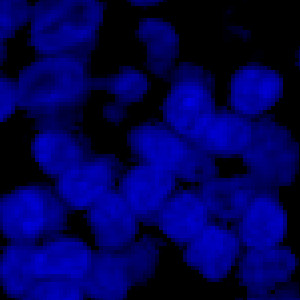

Tissue stained with DAPI

Developed for automatic segmentation of nuclei in fluorescence

Identification and segmentation of individual nuclei is of interest in many applications. Nuclei can be difficult to detect accurately and precisely across different images using traditional image analysis with feature engineering. This APP utilizes artificial intelligence (AI) for automatic nuclear segmentation in fluorescence images stained with a family of blue dyes for DNA identification. It consists of a pre-trained deep neural network and the APP is ready for use without additional training.

The APP was trained using 41,000 annotated nuclei from DAPI stained tissue. The architectural structure of the network is a U-Net which is popular for medical image segmentation. The neural network uses a cascade of layers of nonlinear processing units for feature extraction and transformation, with each successive layer using the output from the previous layers as input. U-Net uses an encoder-decoder structure with a contracting path and an expansive path. For more information of the network architecture, see [1].

Tissue must be labeled with a blue fluorescent dye for DNA staining such as DAPI, Hoechst or Iridium such that all nuclei are labeled.